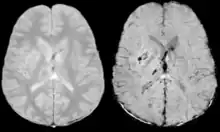

Diffusion weighted imaging offers a powerful means to detect acute stroke. Although it is well known that gradient echo imaging can detect hemorrhage, it is best detected with SWI. In the example shown here, the gradient echo image shows the region of likely cytotoxic edema whereas the SW image shows the likely localization of the stroke and the vascular territory affected (data acquired at 1.5 T).

The bright region in the gradient echo weighted image shows the area affected in this acute stroke example. The arrows in the SWI image may show the tissue at risk that has been affected by the stroke (A, B, C) and the location of the stroke itself (D). The reason that we are able to see the affected vascular territory could be because there is a reduced level of oxygen saturation in this tissue, suggesting that the flow to this region of the brain could be reduced post stroke. Another possible explanation is that there is an increase in local venous blood volume. In either case, this image suggests that the tissue associated with this vascular territory could be tissue at risk. Future stroke research will involve comparisons of perfusion weighted imaging and SWI to learn more about local flow and oxygen saturation.